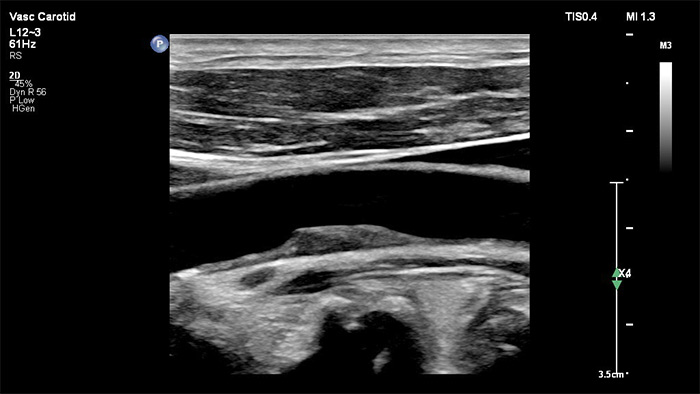

Le traitement nouvelle génération des images de Philips améliore l’imagerie vasculaire en offrant une superbe délimitation des interfaces vasculaires et une meilleure perception de la texture de plaque. En réduisant le flou dans les vaisseaux et les artefacts, XRES Pro améliore la fiabilité du diagnostic lors de la réalisation d’examens d’imagerie vasculaire chez les patients, y compris ceux qui sont techniquement difficiles.

La sonde xMATRIX XL14-3 intègre 56 000 éléments remarquables, chacun connecté à un microcanal séparé. La sonde XL14-3 offre une focalisation électronique multidimensionnelle pour une imagerie échographique en coupes ultrafines de l’anatomie vasculaire et de la morphologie de plaque. Atout majeur : une fiabilité du diagnostic exceptionnelle lors de l’évaluation d’une sténose et d’une plaque vulnérable.